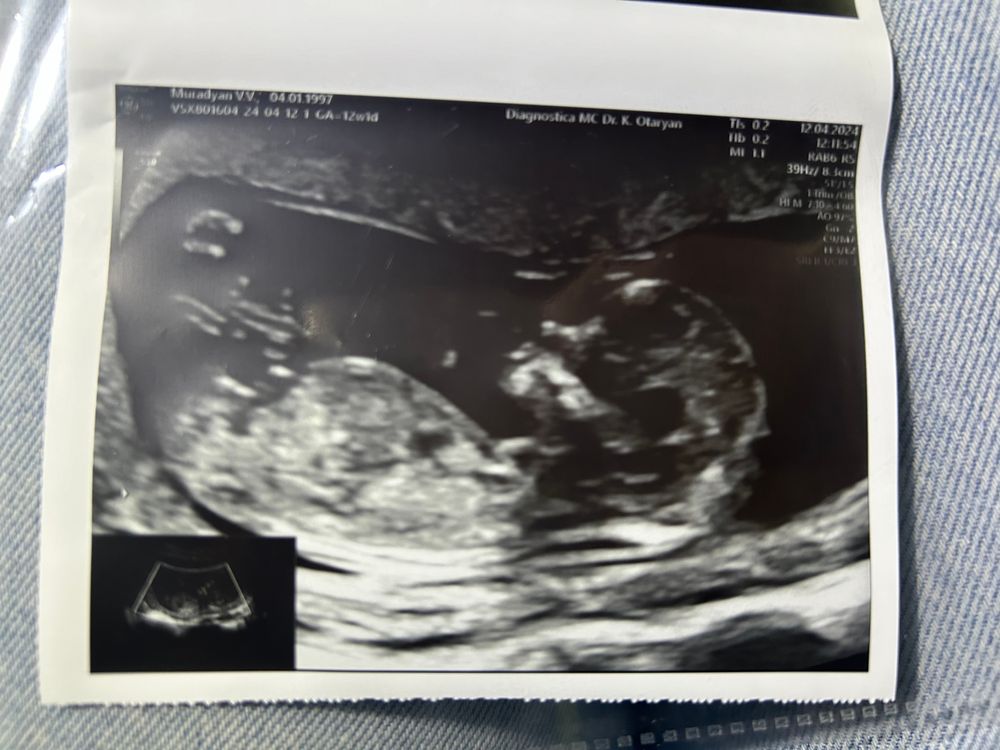

12 недель 1 день, первый скрининг❣️12.04

По развитию опережаем на 5 дней

ЧСС 161 уд/мин

КТР 64 мм

Врач сказала, все отлично развивается, смотрела час, первый скрининг прошли на пятерку)

сказали 95% мальчик, но кто бы ни был, очень ждём и любим 🩶🩶🩶